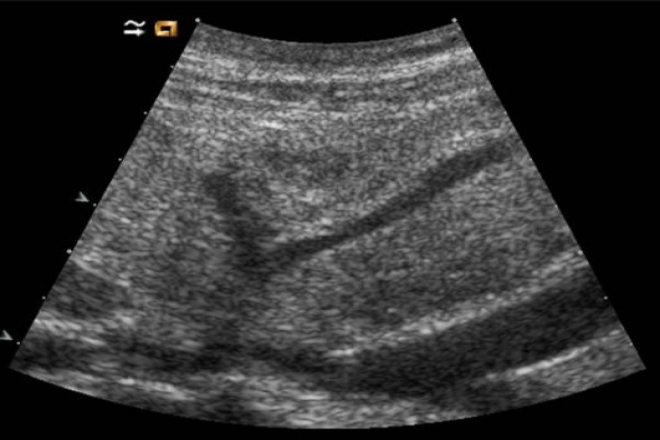

La exploración ecográfica del páncreas debe realizarse  en bipedestación se realizan rastreos transversales  en line media por debajo de apófisis xifoides utilizando  marcas vasculares relacionadas para identificar la región del páncreas.

El rastreo sagital: en transductor línea media por debajo de apófisis xifoides, localizando la confluencia de la vena esplénica y la vena porta, utilizando  el riñón izquierdo se puede visualizar la cola del páncreas.